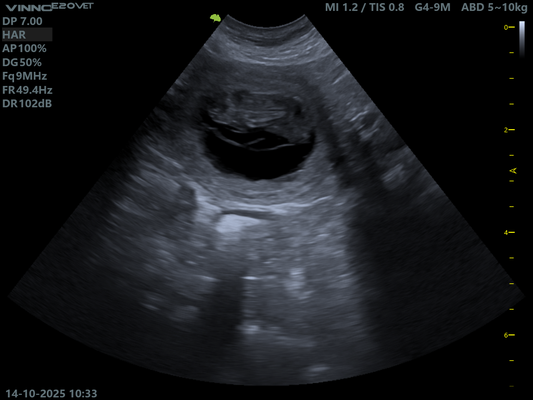

14.10.2025 Ultraschall Untersuchung.

Schon nach einem kurzen Blick in Ruby's Bauch war klar.

Sie ist tragend!

Doch wie viele es werden bleibt bis zuletzt spannend.

Hier müssen wir uns absolut keine Sorgen machen. Ruby scheint einen normalen Wurf zu erwarten, so auch die Aussage unserer Tierärztin.